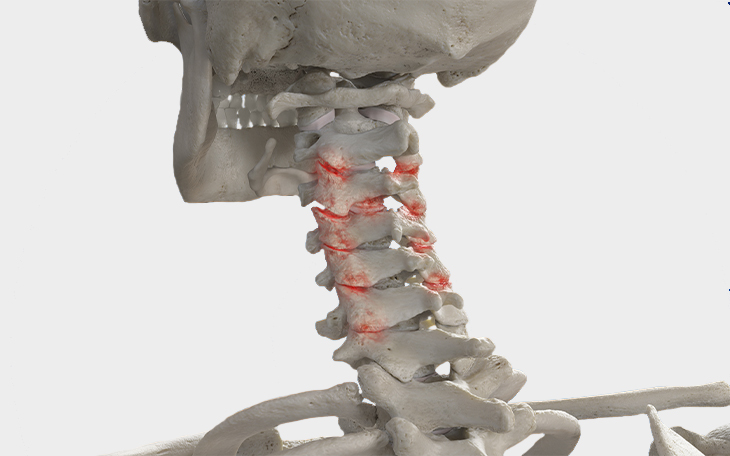

Erkrankungen der Halswirbelsäule

Die Halswirbelsäule (HWS) ist besonders beweglich und zugleich empfindlich gegenüber Fehlbelastungen und Verschleiß. In dieser Kategorie erhalten Sie einen Überblick über häufige Erkrankungen der HWS, deren Ursachen, Symptome und Therapiemöglichkeiten.